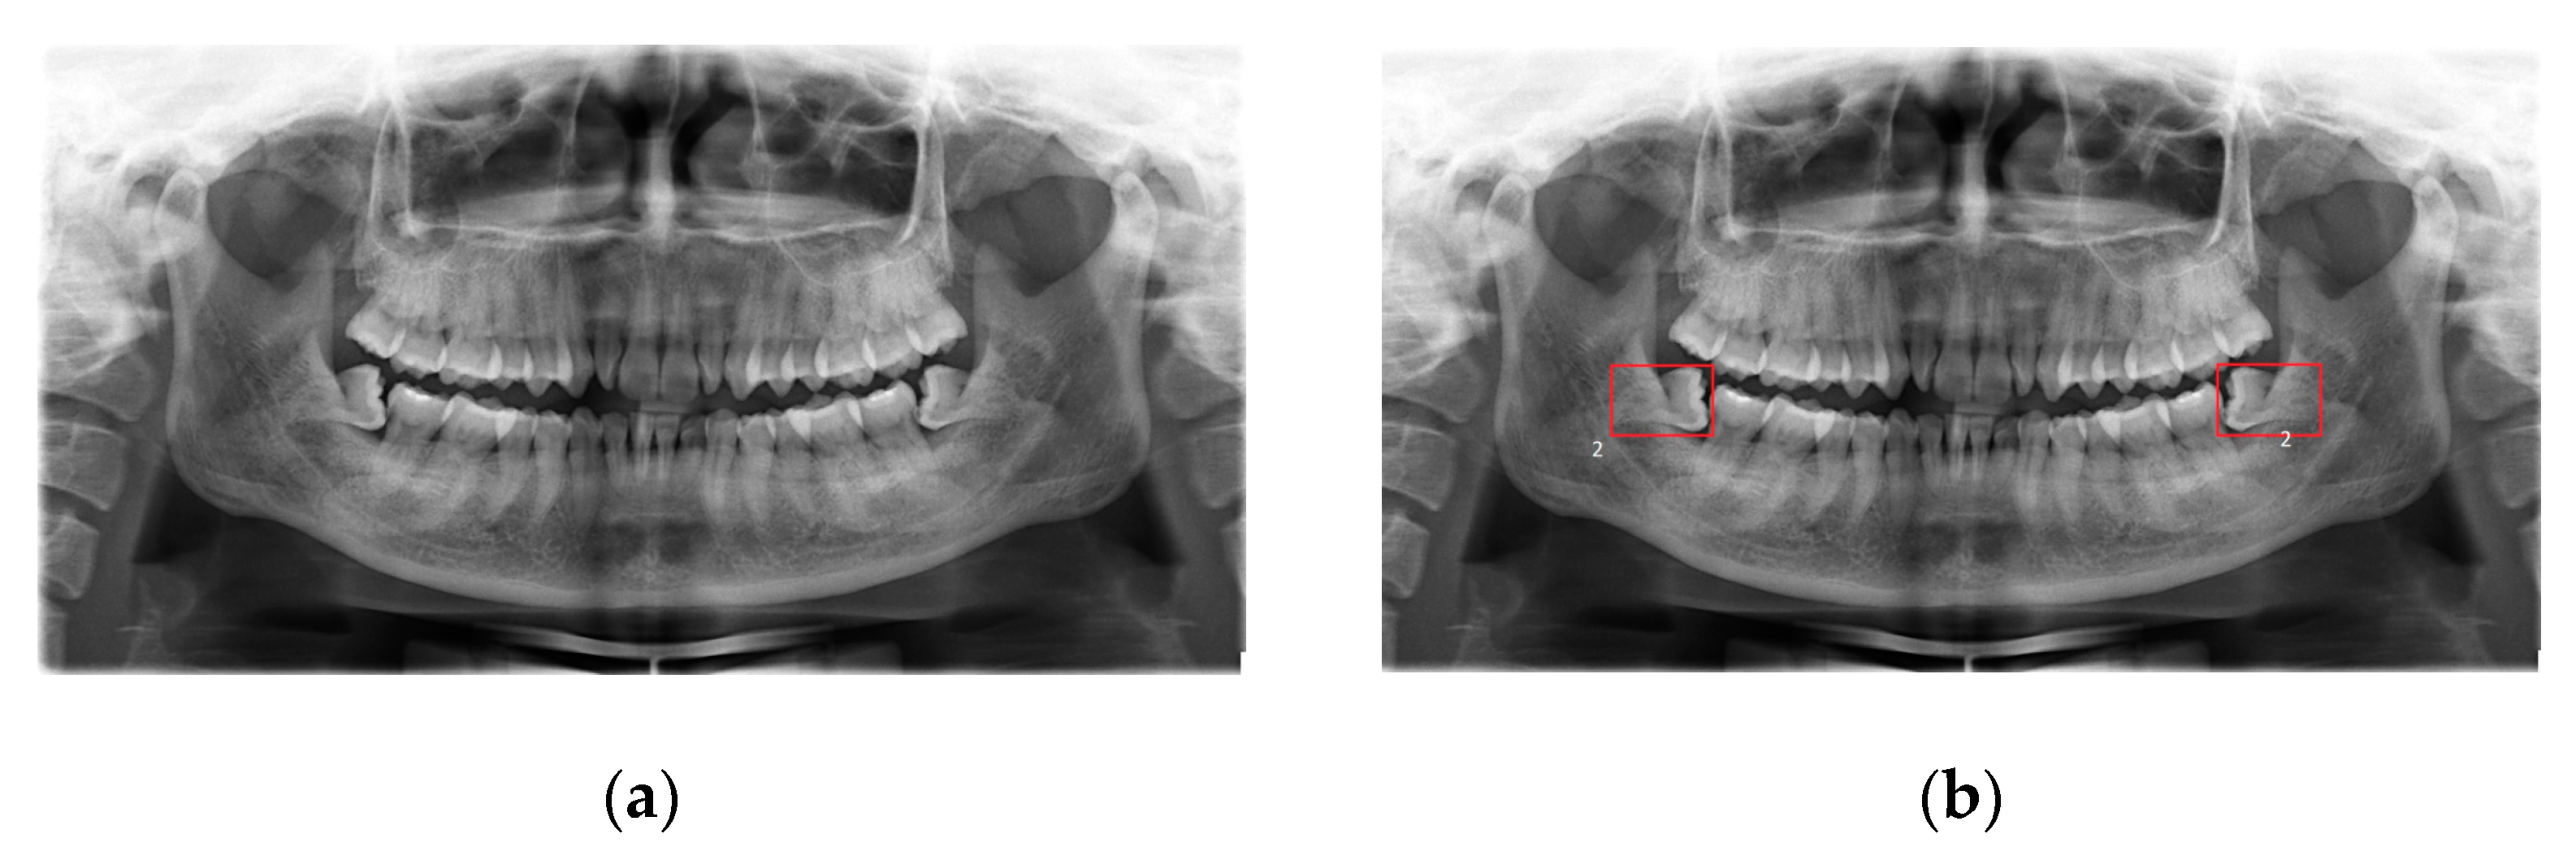

• The fourth dataset is the real dental dataset from Hanoi Medical University Hospital, Vietnam [53], in which dentists provide a properly labeled dataset that consists of 447 X-ray images with the disease of wisdom teeth deviate and 200 X-ray images without wisdom teeth deviate. The dental experts are from Hanoi Medical University and are currently working as professional dentists (Figure 3).

Figure 3. (a) A dental image. (b) The patient’s cavity area image.